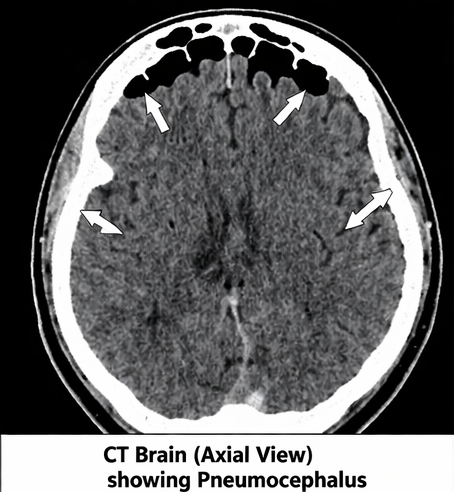

Computed Tomography (CT) Scan of Brain

Non-contrast CT scan revealed:

• Presence of air pockets in the frontal intracranial region

• Air accumulation in the subdural space

• Fracture of the frontal sinus

• No evidence of intracranial hemorrhage

A characteristic “Mount Fuji sign” was absent, suggesting non-tension pneumocephalus.